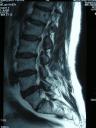

E infatti, quando si ha un trauma con un disco sano, cioè idratato, cioè pieno di acqua, la prima cosa che si rompe è la vertebra, perché il disco sano è “incomprimibile”, sfonda il piatto vertebrale e Ernia nella vertebra stessa. (sui libri si chiama ernia di Schmorl) .

Quando 2 vertebre smettono di muoversi l’una sull’altra, il disco non riceve più nutrimento si disidrata, comincia ad essere “comprimibile” e pian piano, la rete della spugna si sfilaccia sotto la pressione che aumenta; così il disco sotto pressione, si sfianca, si indebolisce e migra, si sposta in un posto che non è il suo. Se manca il movimento, il disco soffre ed eventualmente nel tempo ernia. Bisogna recuperare il movimento, così che chi spinge il disco fuori dal suo posto, smetta di spingere.